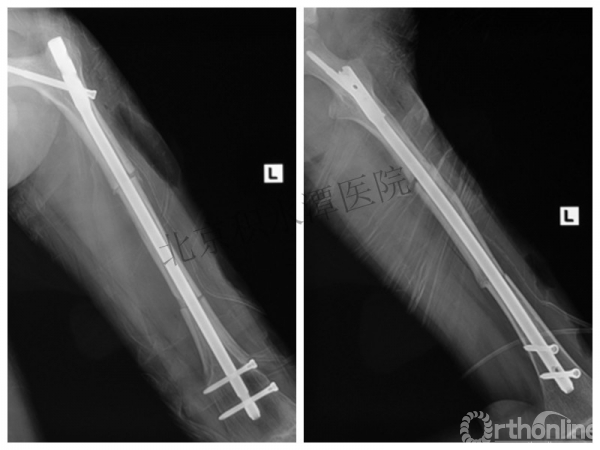

外固定架术后一年

整整11年!是否治疗终结?

病人的付出?医生当反思!

一、思考

1.使用了医生可以使用的所有固定方式

2.似乎哪一次的处理都没有违背原则

3.问题出在哪儿?

4.骨折治疗—手术不是万能的!